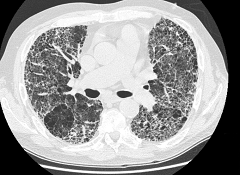

Лимфаденопатия или увеличение лимфатических узлов данного органа наблюдаются при метастазах карциномы, лимфомах, а также некоторых неопухолевых заболеваниях (саркоидозе, туберкулезе и т.д.).

Поражение лимфатических узлов, характерное для лимфом может быть изолированным, так и сочетать собой прорастание опухолей в другие анатомические структуры (трахею, сосуды, бронхи, плевру, пищевод, легкие).